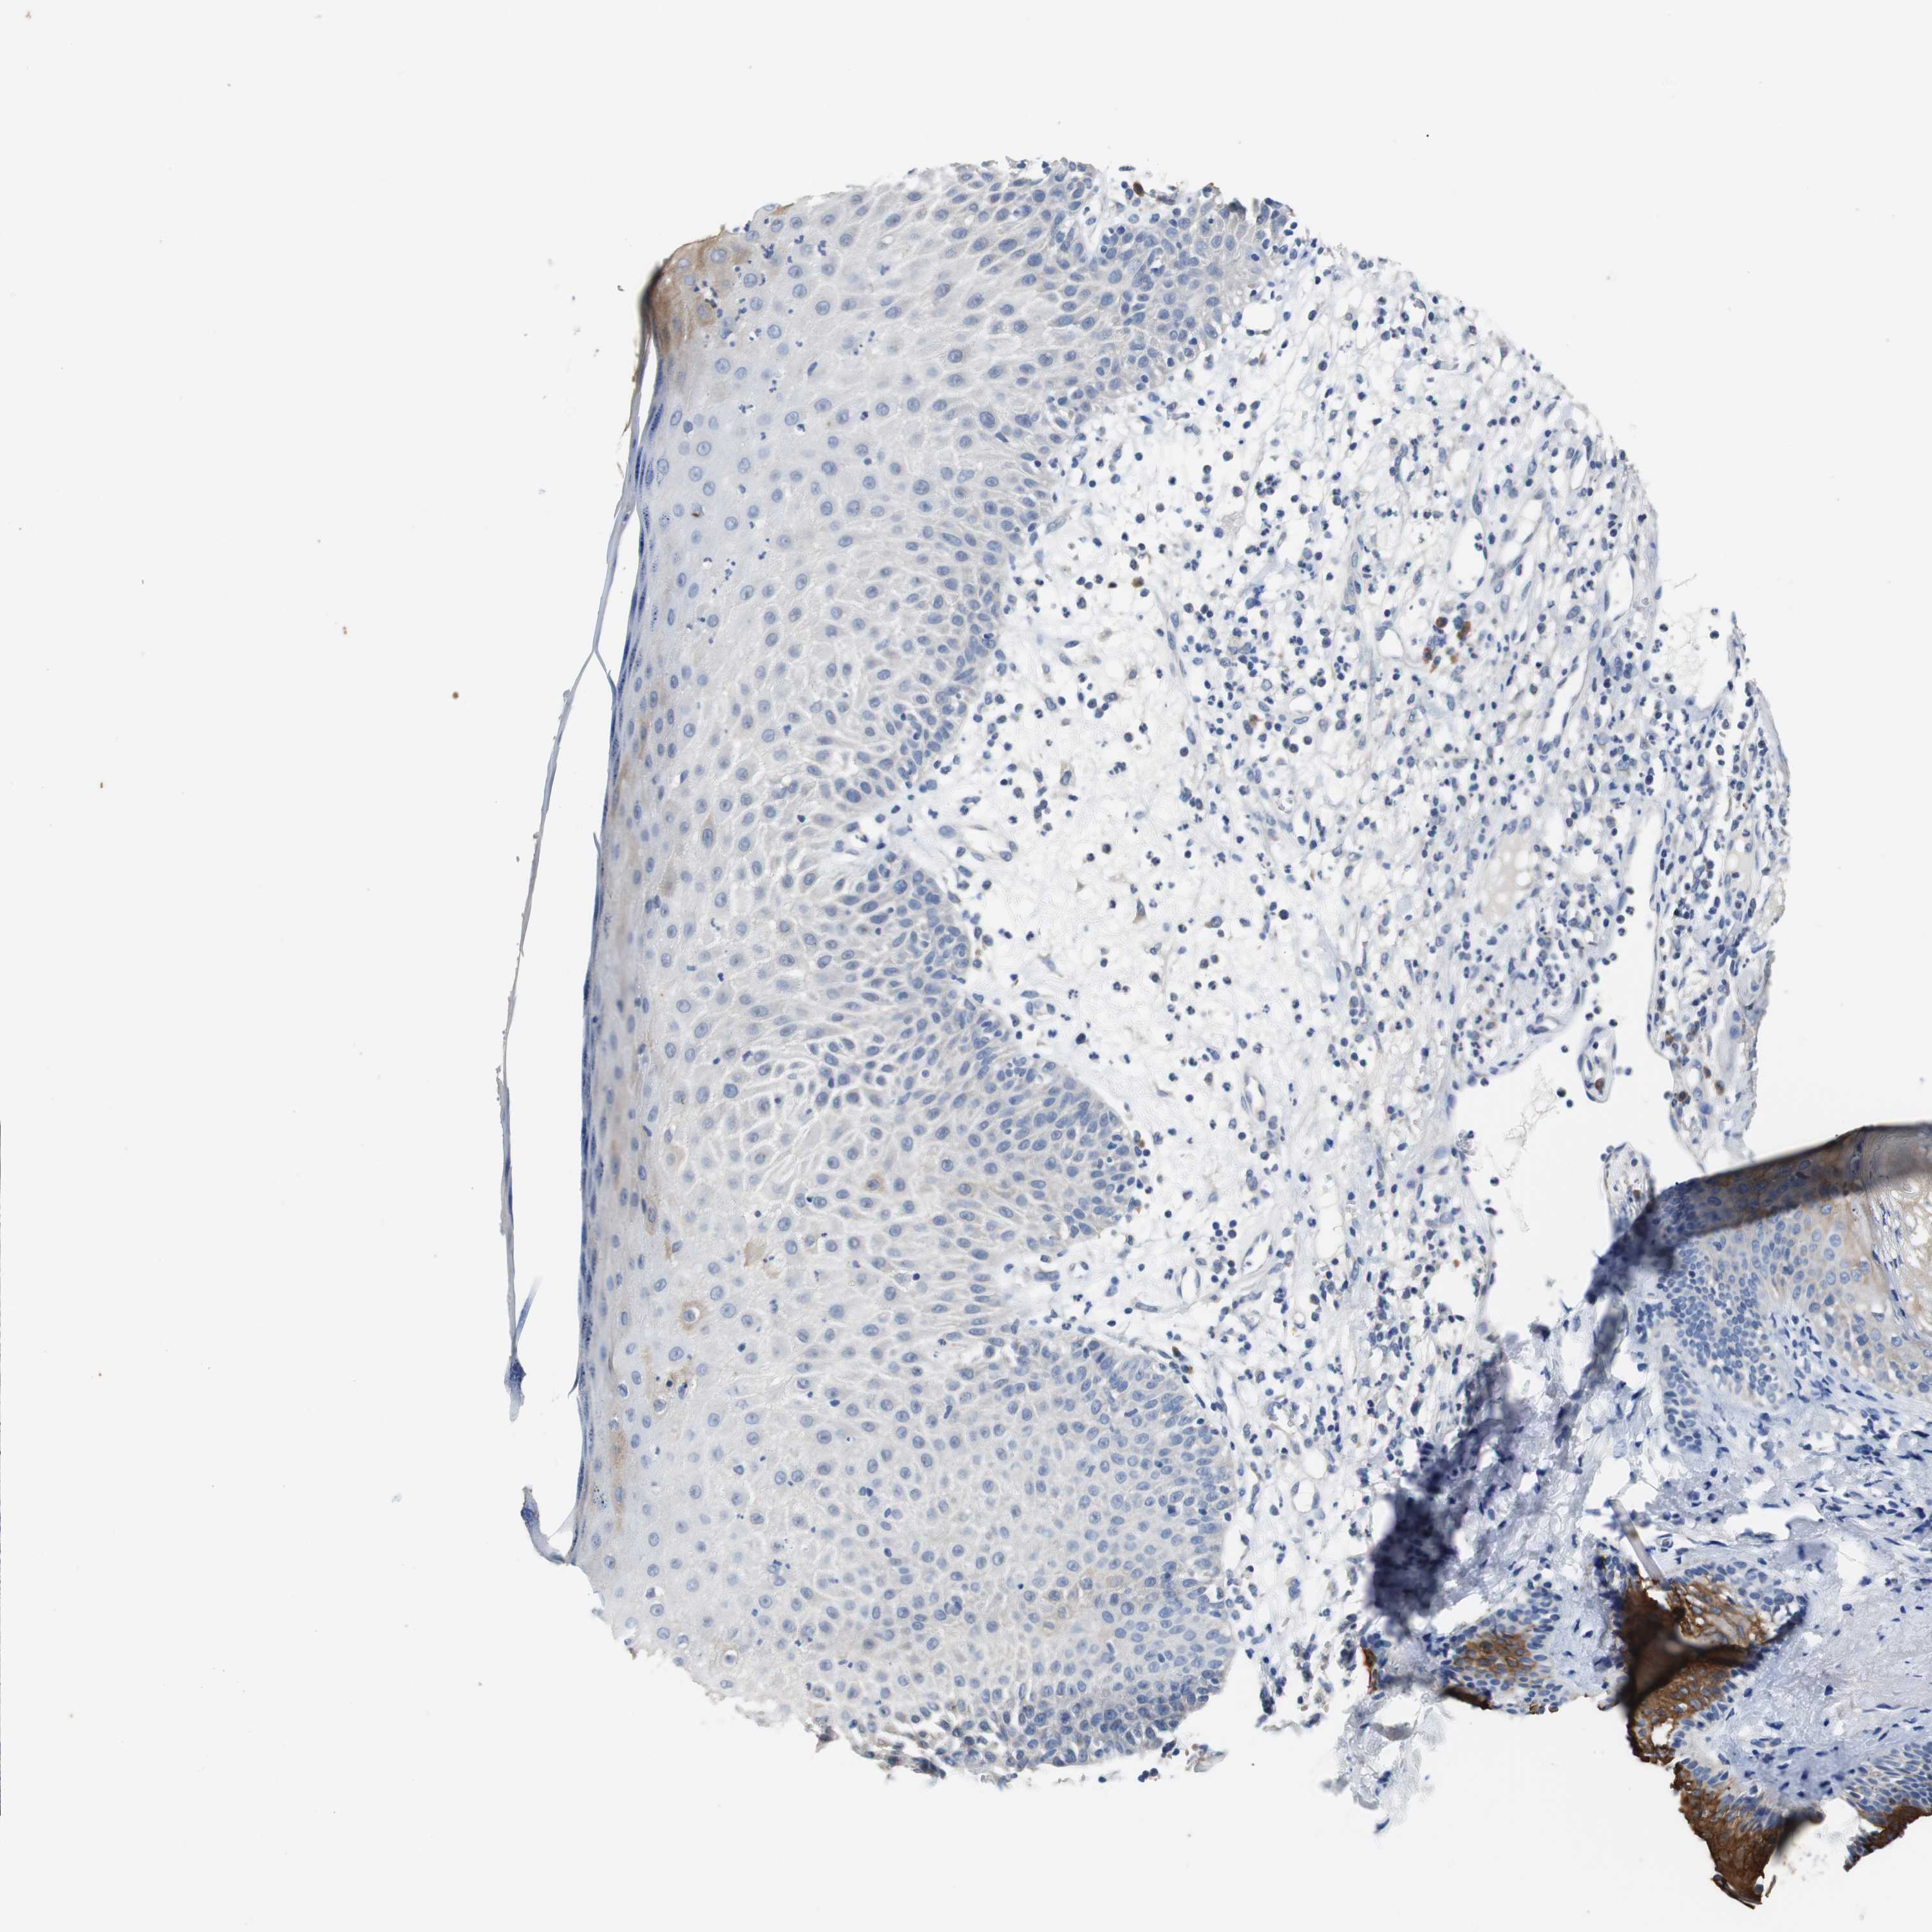

SKIN CANCER - Protein expressioni

A mouse-over function shows sample information and annotation data. Click on an image to view it in a full screen mode. Samples can be filtered based on level of antibody staining by selecting one or several of the following categories: high, medium, low and not detected. The assay and annotation is described here.

Each image is clickable and will lead to virtual microscopy that enables deeper exploration of all samples and also displays staining intensity scores, fraction scores and subcellular localization as well as patient and tissue information for each sample.

Antibody HPA006277

Antibody HPA006507

Antibody CAB017027

Staining

High

Medium

Low

Not detected

Intensity

Strong

Moderate

Weak

Negative

Quantity

>75%

75%-25%

<25%

None

Location

Nuclear

Cytoplasmic/membranous

Cytoplasmic/membranous,nuclear

Squamous cell carcinoma, NOS

Basal cell carcinoma

Squamous cell carcinoma, metastatic, NOS